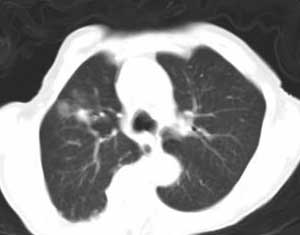

患者,女,69y,居住农村,胸闷,咳嗦,自述无发热,有慢支。患者消瘦,体制弱。

右肺门肿块影,中间段支气管以及右下叶支气管被浸润、堵塞,伴纵隔内淋巴结转移以及阻塞性肺炎。右肺中心型肺癌,堵的还很实在啊

1,右侧中央型肺癌并右下肺不张及纵隔淋巴结转移;

2,慢支,肺气肿;

3,右上肺陈旧性结核.

1 右侧中央型肺癌并右下肺不张及纵隔淋巴结转移;

2 慢支,肺气肿;

3 右上肺病变. 性质:肺癌?转移?炎症?

右肺下叶中心性肺癌,阻塞性肺炎及段性肺不胀。纵隔淋巴结转移。右上肺陈旧性肺结核。

好象有钙化,考虑右下肺中央型肺癌(鳞癌)伴阻塞性改变,纵隔淋巴结转移;

右上肺渗出性改变;慢支肺气肿;胸廓畸形伴肺心病改变.